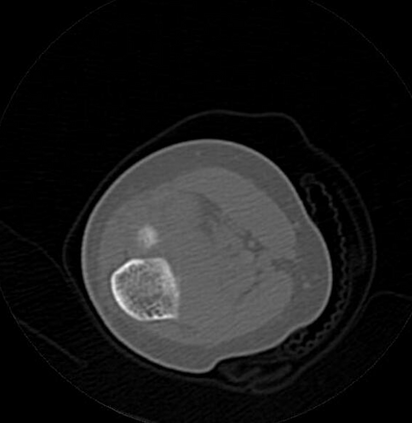

In this study, we aim to initiate the development of Radiology Foundation Model, termed as RadFM.We consider the construction of foundational models from the perspectives of data, model design, and evaluation thoroughly. Our contribution can be concluded as follows: (i), we construct a large-scale Medical Multi-modal Dataset, MedMD, consisting of 16M 2D and 3D medical scans. To the best of our knowledge, this is the first multi-modal dataset containing 3D medical scans. (ii), We propose an architecture that enables visually conditioned generative pre-training, allowing for the integration of text input interleaved with 2D or 3D medical scans to generate response for diverse radiologic tasks. The model was initially pre-trained on MedMD and subsequently domain-specific fine-tuned on RadMD, a radiologic cleaned version of MedMD, containing 3M radiologic visual-language pairs. (iii), we propose a new evaluation benchmark that comprises five tasks, aiming to comprehensively assess the capability of foundation models in handling practical clinical problems. Our experimental results confirm that RadFM significantly outperforms existing multi-modal foundation models. The codes, data, and model checkpoint will all be made publicly available to promote further research and development in the field.